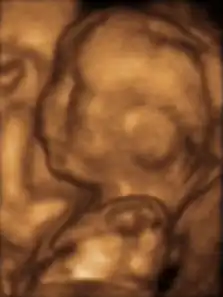

Feto de 13 semanas

Feto humano